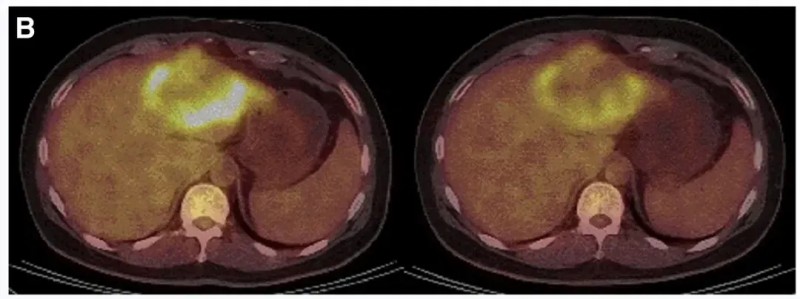

一例P9-2患者:在接受CEA CAR-T回输后,PET/CT显示肿瘤活动减弱、代谢活性显著降低。下图展示了CAR-T输注前(左图)、治疗4周后(右图)的PET/CT对比。

▲图源“Molecular Therapy”,版权归原作者所有,如无意中侵犯了知识产权,请联系我们删除